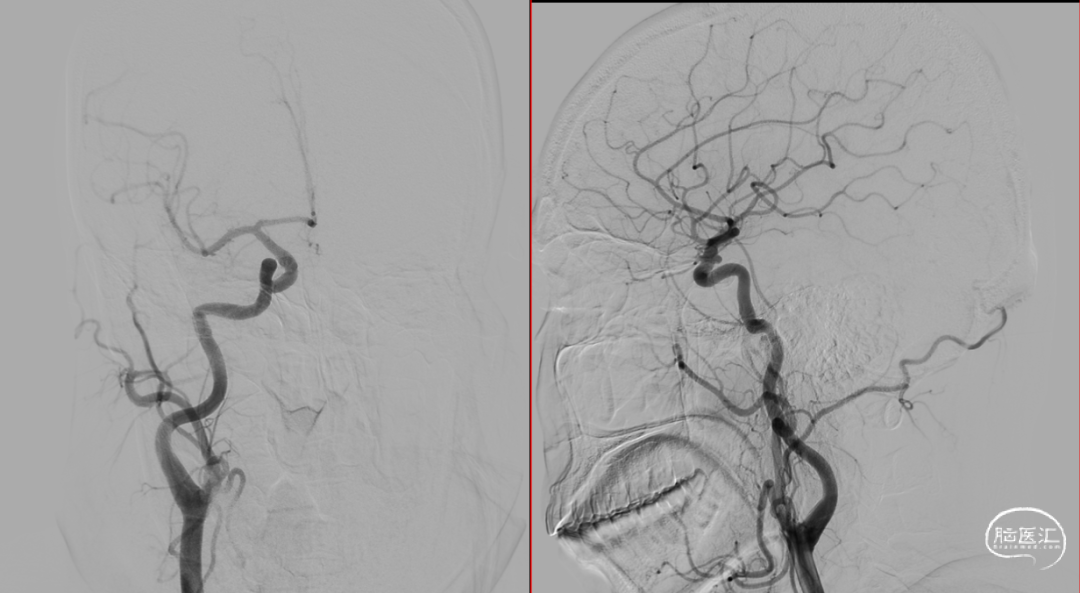

CTA:右侧颈内动脉C6段动脉瘤。

DSA:DSA提示右侧颈内动脉C6段可见多发动脉瘤。

其他血管造影未见明显异常。

术前诊断:右侧颈内动脉C6段多发动脉瘤。